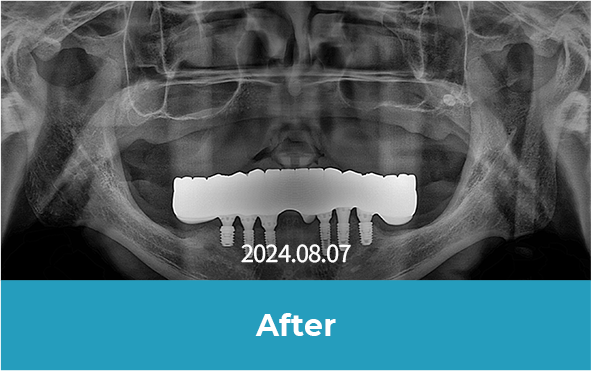

All-on-x는 4~6개의 임플란트만으로

전체 치아를 지지하는 방식으로 진행됩니다.

기존 전체 임플란트 대비 식립 개수를 줄이면서도

안정적인 지지력을 확보할 수 있어

틀니의 불편함 없이 자연스러운 저작이 가능합니다.

치료 후 사진

[ 환자분의 동의서 작성 후 게시하였습니다 ]